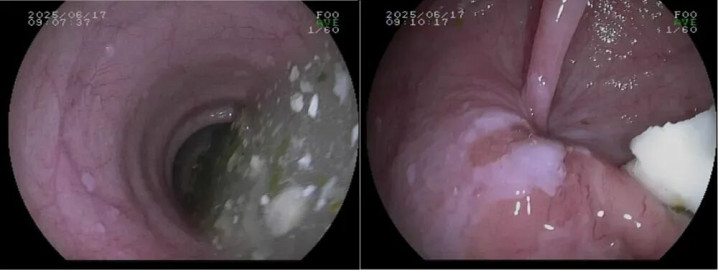

3.胃镜检查

诊断贲门失弛缓症和排除肿瘤的“侦察兵”,食管可能明显变粗(扩张),严重时像被撑大的水管,甚至出现弯曲扭曲,不像正常食管那样笔直通畅。

其次,扩张的食管里常残留食物残渣和黏液,黏膜被长期浸泡得发红水肿。最关键的是贲门,医生把胃镜往胃里送时,会明显感觉这里阻力很大,像推一扇锈死的门——正常贲门碰到胃镜会自然放松,这里却僵着,得突破阻力才能慢慢通过。

不过和肿瘤不同,贲门和食管的黏膜表面一般没有溃疡、肿块这些异常凸起,主要问题是“门打不开”和“通道变形”,不是“长了坏东西”。

胃镜:食管扭曲扩张、食物残渣和黏液潴留,贲门紧闭,胃镜通过阻力明显。